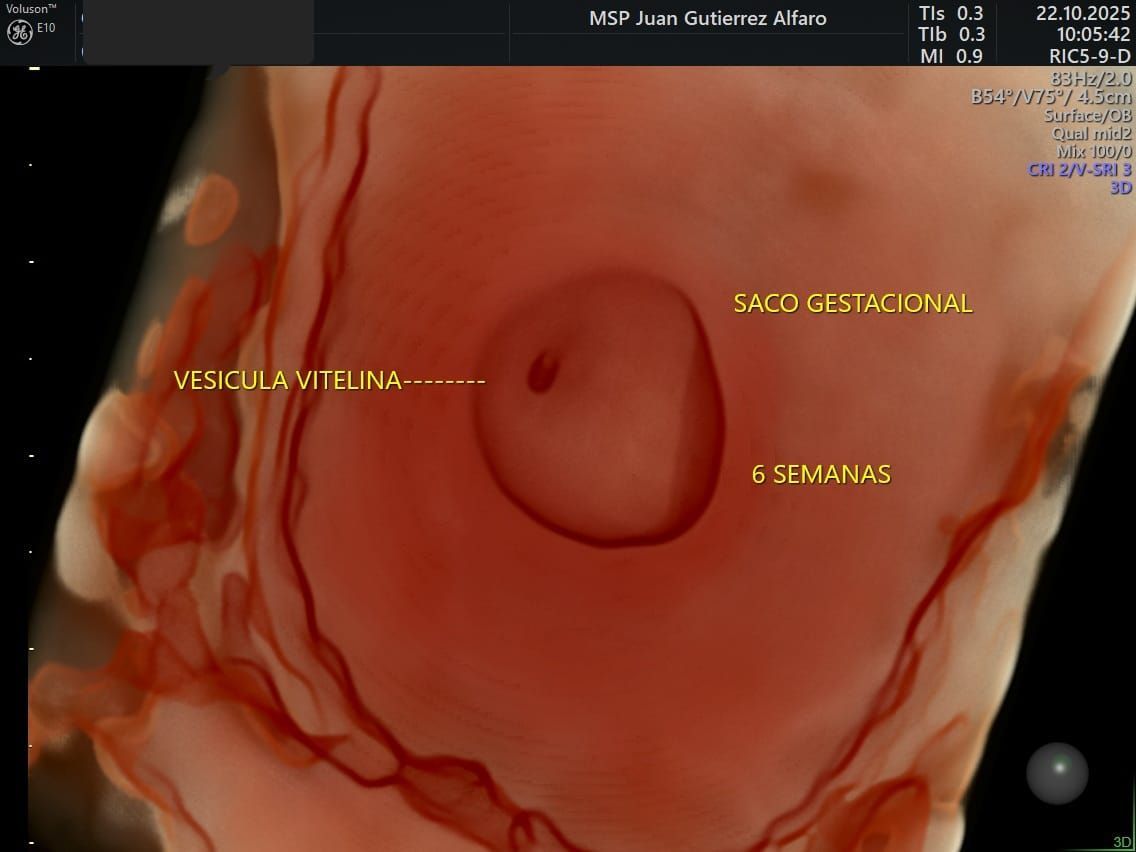

ECOGRAFÍAS - 7 D

- HDlive Silhouette - 7 D